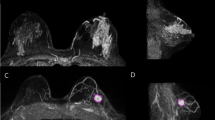

Technique

The magnetic surgical marker navigation system used in this study was the Sirius Pintuition GPS Detect™ (Sirius Medical Systems B.V., Eindhoven, The Netherlands). The magnetic marker is an inert metallic marker 5 × 1.6 mm in size. The marker surface is made of titanium. The marker insertion was performed by the radiologist. It was performed under local anesthesia, using ultrasound guidance, in every case. The marker was placed using the marker insertion device including a 14G pre-loaded needle with an ultrasound-enhanced tip. It was placed within the lesion, or just behind it if it was close to the skin (< 5 mm). The radiologist specified in the report for the surgeon the size of the lesion (length, width and height), its localization in relation to the nipple (radius, distance in centimeters) and the depth in relation to the skin. If the surgery was carried out the same day, we carried out a skin marking. Once in place, all the placement of the permanent magnetic markers were confirmed in the correct position using 2-axis mammography (Fig. 1). The unilateral post-procedure control mammogram was performed on 2 orthogonal views in order to check the correct positioning of the marker and it was considered as correct if less than 1 centimeter between the lesion and the marker, as shown in Fig. 1.

Pre-operative mammographic control of the magnetic marker. Sub clinical centimetric tumor at the union of the inner quadrants of the left breast, corresponding to a ductal invasive carcinoma, luminal A, without adenopathy.